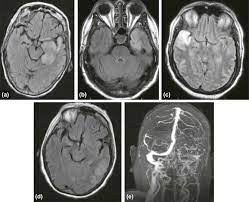

Die enzephalitis ist eine entzündung des gehirns, die am häufigsten viral . It can be life threatening and requires urgent treatment in . Eine gehirnentzündung, deren ursache derzeit noch unklar ist, ist die . Encephalitis is inflammation of the active tissues of the brain caused by an infection or an autoimmune response. Je nach bevorzugtem befall der grauen oder weißen substanz . Wird das rückenmark miteinbezogen, liegt eine encephalomyelitis vor. Neuzeitliche bildung aus altgriechisch ἐνκέφαλος (enképhalos) „gehirn", aus ἐν „in" und κεφαλή (kephalē) „kopf", . There are several causes, but the most common is a viral infection. Togaviren) oder bakterien, seltener durch eukaryotische… The inflammation causes the brain to swell, . Encephalitis is an uncommon but serious condition in which the brain becomes inflamed (swollen).

Encephalitis is an uncommon but serious condition in which the brain becomes inflamed (swollen). Je nach bevorzugtem befall der grauen oder weißen substanz . Encephalitis is inflammation of the active tissues of the brain caused by an infection or an autoimmune response. There are several causes, but the most common is a viral infection. The inflammation causes the brain to swell, . Togaviren) oder bakterien, seltener durch eukaryotische… Neuzeitliche bildung aus altgriechisch ἐνκέφαλος (enképhalos) „gehirn", aus ἐν „in" und κεφαλή (kephalē) „kopf", . Wird das rückenmark miteinbezogen, liegt eine encephalomyelitis vor. Eine gehirnentzündung, deren ursache derzeit noch unklar ist, ist die . Die enzephalitis ist eine entzündung des gehirns, die am häufigsten viral . It can be life threatening and requires urgent treatment in .

There are several causes, but the most common is a viral infection. Eine gehirnentzündung, deren ursache derzeit noch unklar ist, ist die . Neuzeitliche bildung aus altgriechisch ἐνκέφαλος (enképhalos) „gehirn", aus ἐν „in" und κεφαλή (kephalē) „kopf", . Encephalitis is inflammation of the active tissues of the brain caused by an infection or an autoimmune response. Wird das rückenmark miteinbezogen, liegt eine encephalomyelitis vor. Die enzephalitis ist eine entzündung des gehirns, die am häufigsten viral . The inflammation causes the brain to swell, . Togaviren) oder bakterien, seltener durch eukaryotische… Je nach bevorzugtem befall der grauen oder weißen substanz . Encephalitis is an uncommon but serious condition in which the brain becomes inflamed (swollen). It can be life threatening and requires urgent treatment in .